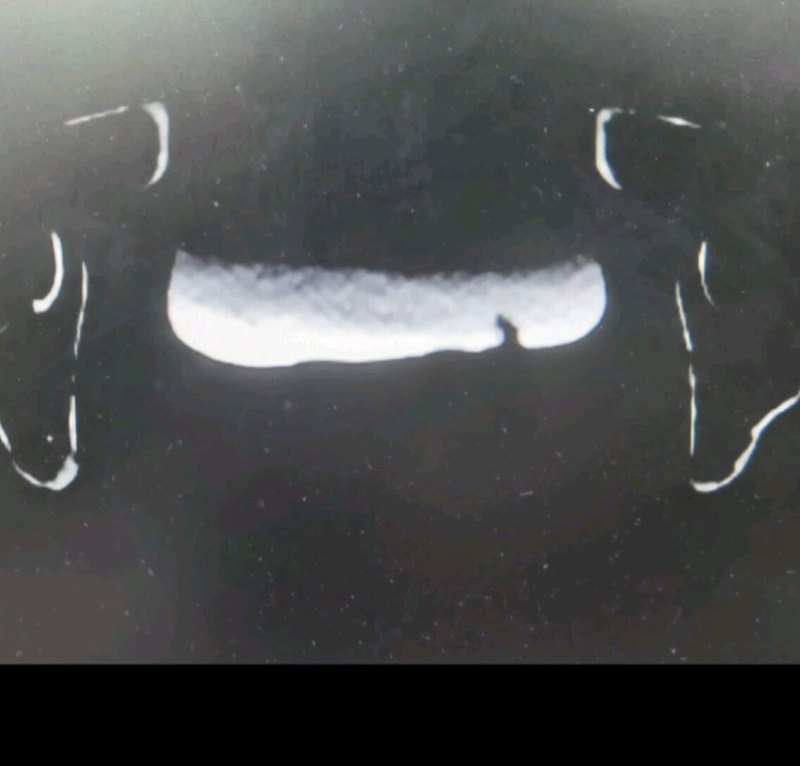

医生如何区分膀胱肿瘤和膀胱结石

许清泉主任医师 北京大学人民医院 泌尿外科

228人已读